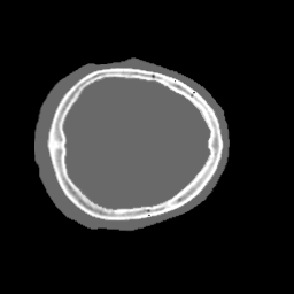

Model-based treatment planning for transcranial ultrasound therapy typically involves mapping the acoustic properties of the skull from an x-ray computed tomography (CT) image of the head. Here, three methods for generating pseudo-CT images from magnetic resonance (MR) images were compared as an alternative to CT. A convolutional neural network (U-Net) was trained on paired MR-CT images to generate pseudo-CT images from either T1-weighted or zero-echo time (ZTE) MR images (denoted tCT and zCT, respectively). A direct mapping from ZTE to pseudo-CT was also implemented (denoted cCT). When comparing the pseudo-CT and ground truth CT images for the test set, the mean absolute error was 133, 83, and 145 Hounsfield units (HU) across the whole head, and 398, 222, and 336 HU within the skull for the tCT, zCT, and cCT images, respectively. Ultrasound simulations were also performed using the generated pseudo-CT images and compared to simulations based on CT. An annular array transducer was used targeting the visual or motor cortex. The mean differences in the simulated focal pressure, focal position, and focal volume were 9.9%, 1.5 mm, and 15.1% for simulations based on the tCT images, 5.7%, 0.6 mm, and 5.7% for the zCT, and 6.7%, 0.9 mm, and 12.1% for the cCT. The improved results for images mapped from ZTE highlight the advantage of using imaging sequences which improve contrast of the skull bone. Overall, these results demonstrate that acoustic simulations based on MR images can give comparable accuracy to those based on CT.